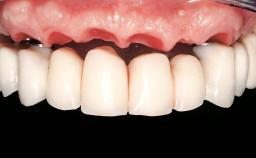

Conventional Loading of Eight Implants in the Maxilla and Final Restoration with a Full-Arch Gold-Ceramic FDP

A 35-year-old Caucasian female presenting with advanced periodontal disease involving both the maxillary and the mandibular dentition was referred for evaluation. The patient, a non-smoker in good general health, requested treatment for recurrent periodontal abscesses, tooth mobility, and discomfort during chewing, as well as restoration of her missing teeth with a fixed prosthesis to improve mastication and esthetics. All residual maxillary teeth exhibited plaque deposits, deep pockets, bleeding on probing, and class III mobility and were evaluated as hopeless. All residual mandibular teeth except tooth 37 could be maintained after periodontal therapy.

| Defining Characteristics | Fully edentulous upper jaw to be rehabilitated with an implant-borne fixed dental prosthesis |

| Loading Protocol | Conventional or early |